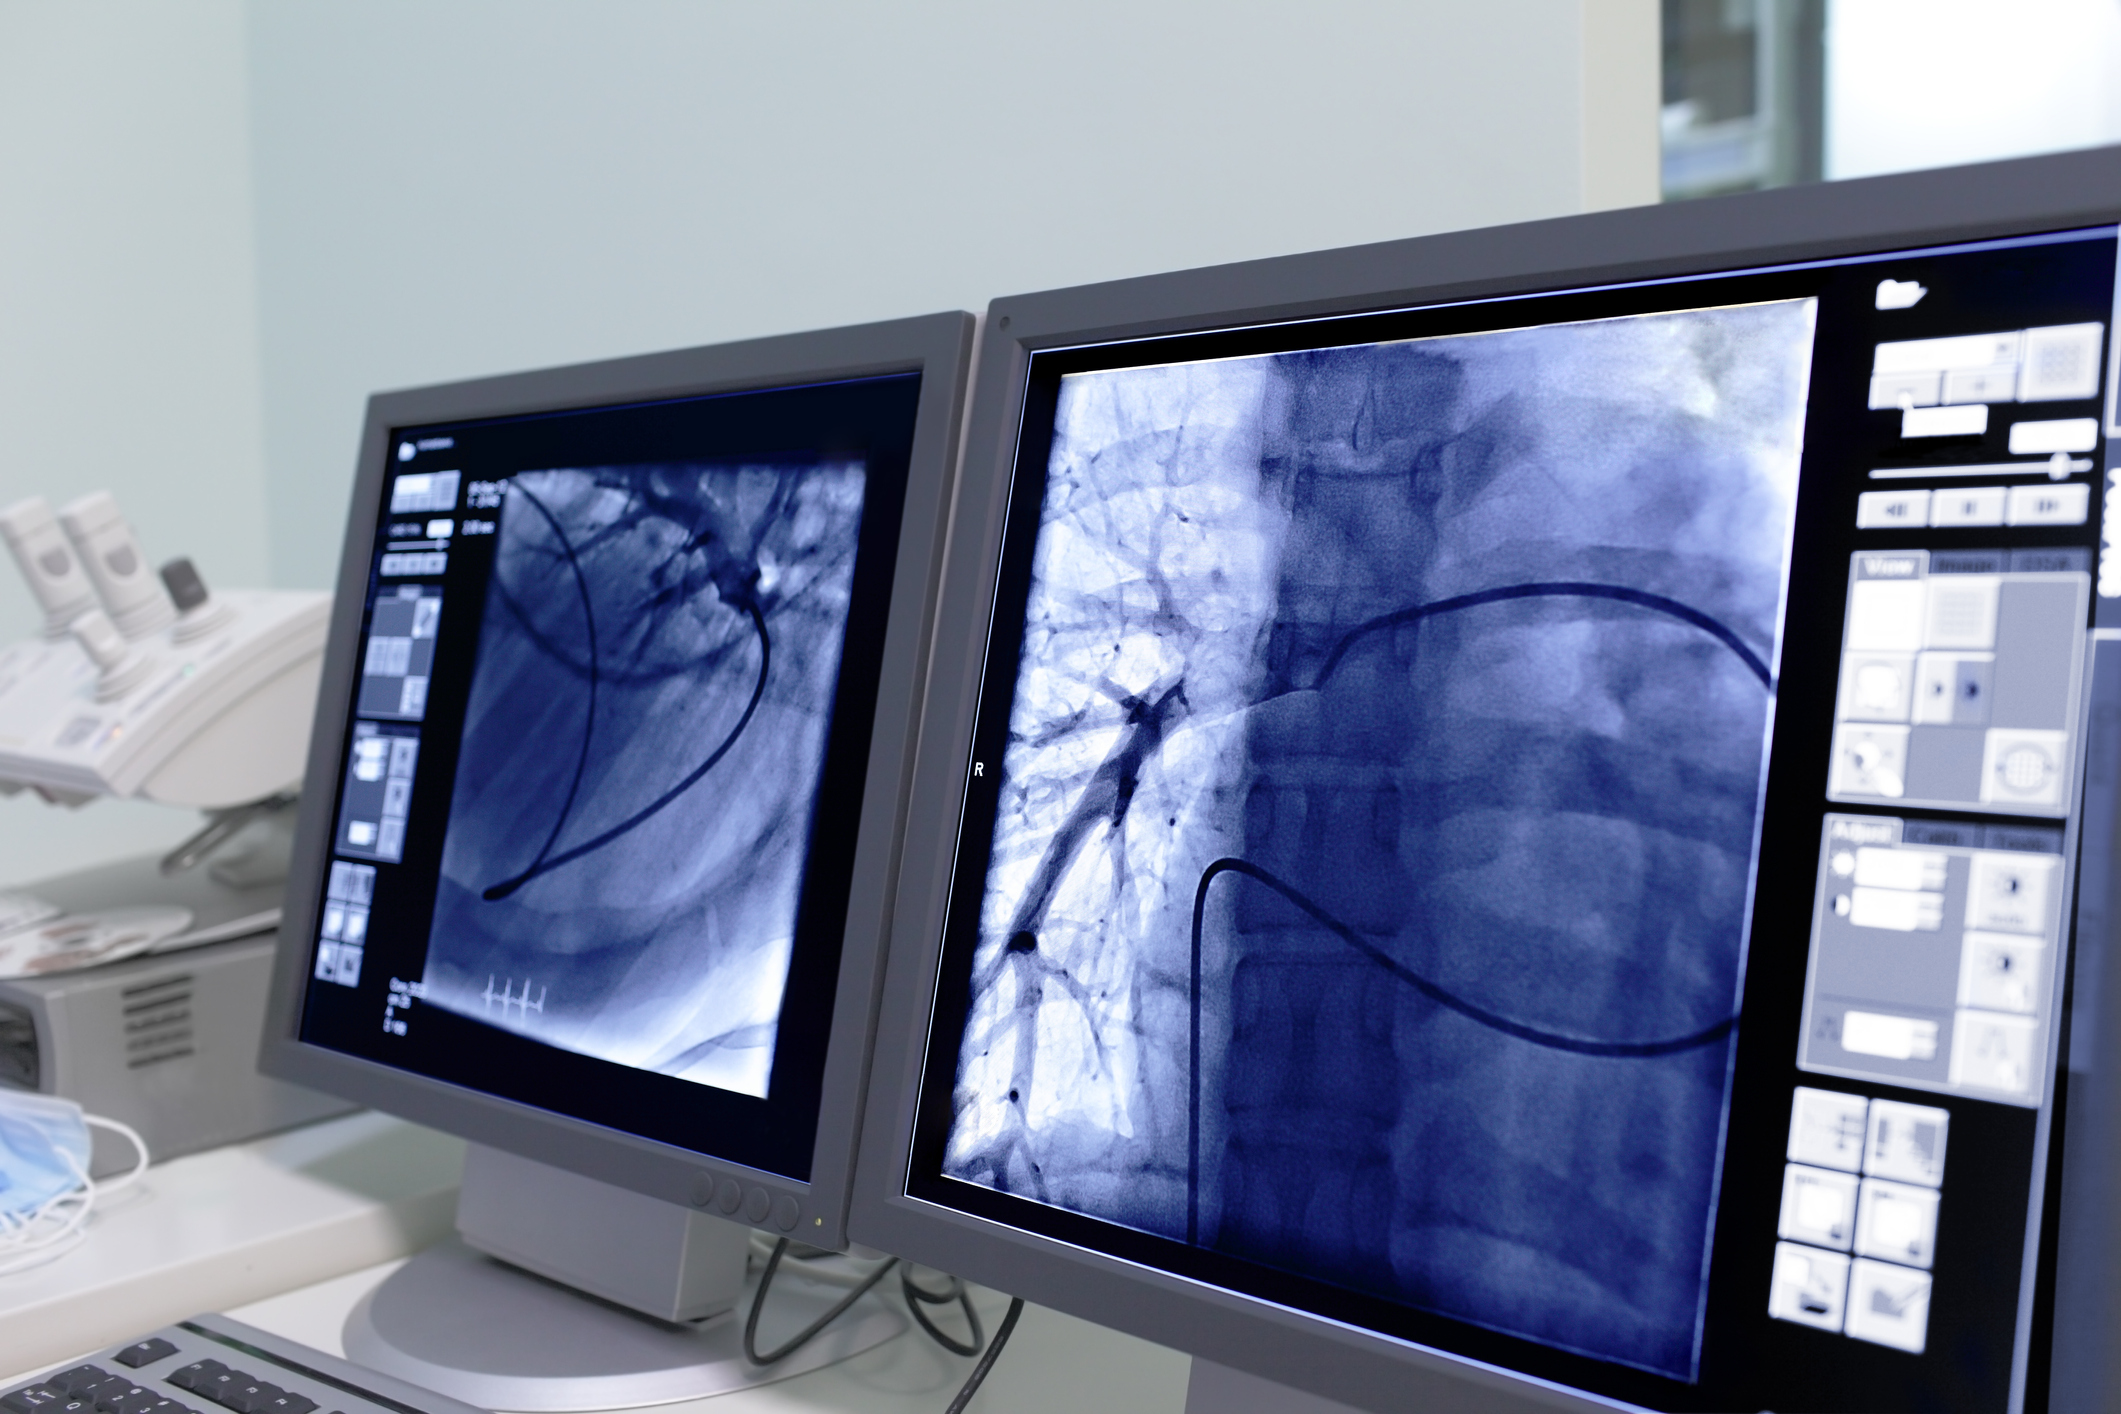

Percutaneous Coronary Intervention (PCI) Cath Lab Procedures Cardiocare

Percutaneous Coronary Intervention (PCI) Cath Lab Procedures Cardiocare Catheterization Lab Pci perform a percutaneous coronary intervention (pci) such as coronary angioplasty with stenting to open up. the aim of this present review is to highlight common preprocedure, intraprocedure, and postprocedure. percutaneous coronary intervention (pci) is the preferred emergency reperfusion strategy in most cases of st. although lack of cardiac surgical support is sometimes considered an absolute contraindication. Catheterization Lab Pci.

Percutaneous Coronary Intervention PCICardiac Catheterization with Catheterization Lab Pci percutaneous coronary intervention (pci) is the preferred emergency reperfusion strategy in most cases of st. perform a percutaneous coronary intervention (pci) such as coronary angioplasty with stenting to open up. the aim of this present review is to highlight common preprocedure, intraprocedure, and postprocedure. although lack of cardiac surgical support is sometimes considered an absolute contraindication. Catheterization Lab Pci.